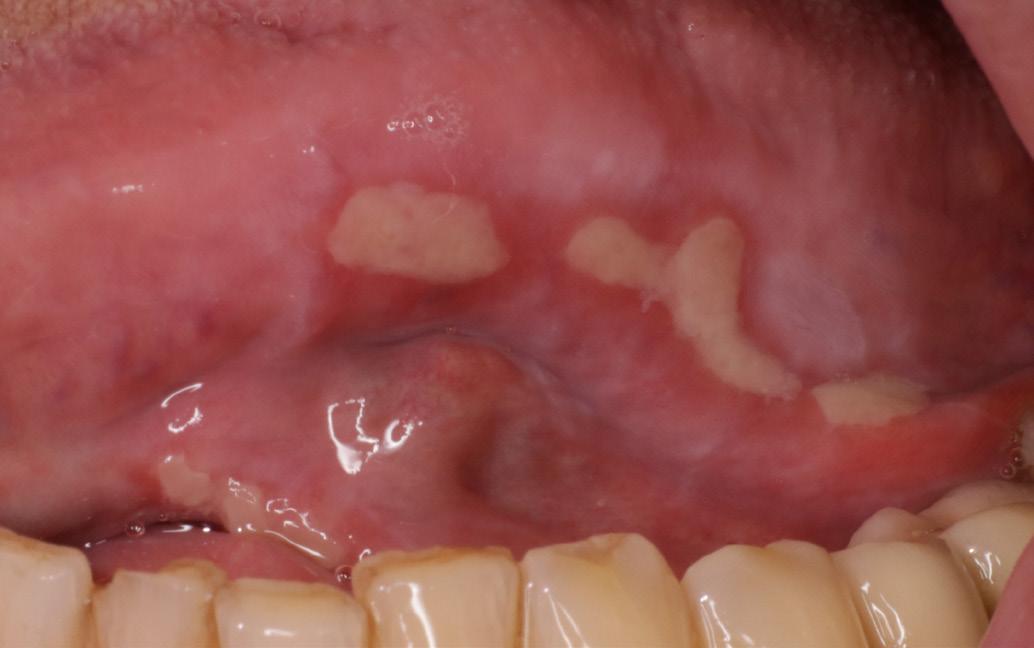

A 78-year-old male with a 10-year history of rheumatoid arthritis presented to the Oral Medicine Clinic with multiple painful oral ulcers of two weeks’ duration. He had been taking methotrexate 20 mg once weekly along with 5 mg folic acid daily.

Oral examination revealed several shallow ulcers with erythematous borders affecting the buccal mucosa and the lateral borders of the tongue (Fig. 1). The patient reported significant discomfort while eating and speaking. Blood investigations were unremarkable. He was prescribed dexamethasone mouthwash and Difflam rinse, but there was no improvement. Methotrexate-induced oral ulceration was suspected. The patient’s rheumatologist was contacted, and methotrexate was temporarily withheld. Supportive therapy

Case 1

Fig. 1

Multiple painful ulcers on the buccal mucosa and lateral border of the tongue in a patient taking low-dose methotrexate.